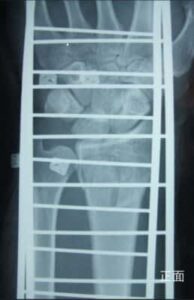

第16回整骨研究会「賜恩」研修会開催

さわやか千葉県民プラザ(指骨骨折)

第18回整骨研究会「賜恩」研修会開催